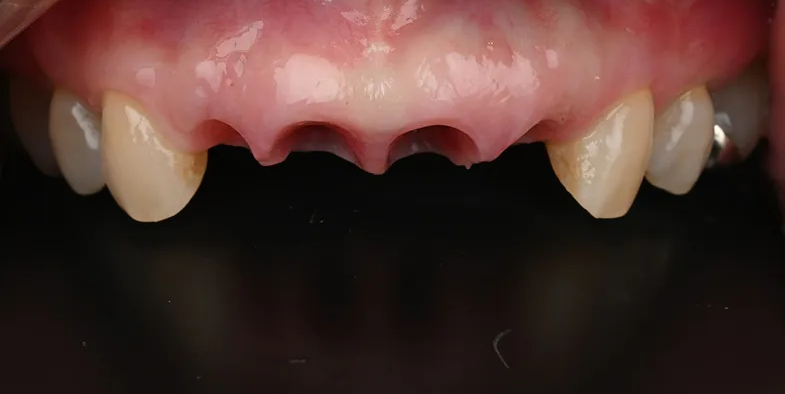

Case2

術前

術中

術後

| 治療名 | 右上1、2:前歯インプラント 右上3、左上1:セラミッククラウン |

|---|---|

| 治療説明 | 右上1の歯根破折により抜歯が必要となったため右上1と2の2本にインプラントで歯を補うことを計画しました。右上1に抜歯と同時にインプラントを埋入し、右上2はもともと歯が欠損して歯肉が凹んでいたため、結合組織移植を行い歯肉のボリュームを回復しました。仮歯で歯肉の形を整えてセラミックの歯を装着しました。 |

| 治療回数・期間 | 6ヶ月 |

| 副作用とリスク | 入れ歯やブリッジと比べて治療期間が長くかかることがあります。インプラント手術と結合組織移植は、違和感、痛み、腫れ、出血などが発生する場合があります。一時的なもので、2日〜1週間で治まります。 |

| 料金(税込) | 骨造成:110,000円 インプラント1次手術:220,000円 インプラント2次手術:55,000円 結合組織移植:110,000円 上部構造:220,000円(2本:440,000円 セラミッククラウン:132,000円(2本:264,000円) 合計:1,199,000円 |